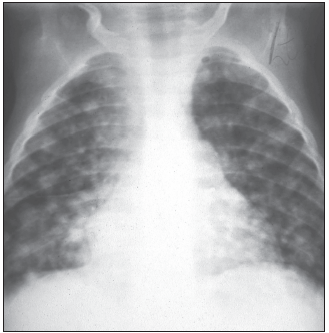

Progressive pulmonary TB develops if the primary complex does not heal or calcify. The complex enlarges and forms a large caseous necrotic center, which may empty into a bronchus, leaving behind a cavity (Figure 7). Subcarinal nodes may drain into the pericardial sack causing tuberculous pericarditis. Serofibrinous exudates eventually lead to fibrosis of the pericardium and constrictive pericarditis with superior and inferior vena cava congestion, hepatomegaly, and ascites (Figure 8).3

Lymphohematogenous spread of TB in children occurs early in the incubation period. It may remain occult and manifest months later as extrapulmonary TB. It may also manifest clinically as overwhelming miliary TB--typically in infants within the first few weeks after infection. Miliary TB may also be the consequence of a tuberculous focus (typically a lymph node) draining into a blood vessel. In patients with miliary TB, numerous lesions can be found in the lungs, liver, spleen, skin, bone marrow, myocardium, and brain (Figure 9).4